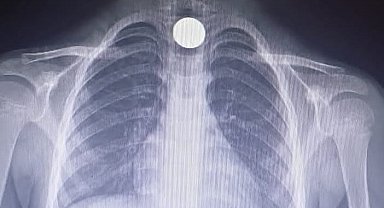

Yusuf'un yemek borusuna takılan madeni para operasyonla çıkartıldı